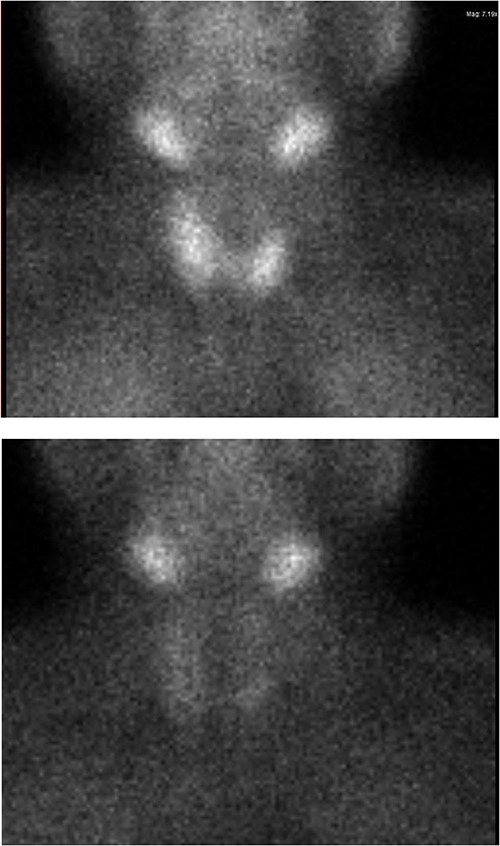

Ultrasound of the neck (Fig. 1), CT and parathyroid sestamibi scan (Fig. 2) failed to localize parathyroid, and all studies showed normal thyroid with no other neck masses or suspicious lymph nodes. Magnetic resonance imaging neck showed no evidence of parathyroid adenoma in the expected typical gland locations or ectopic cervical or upper mediastinum. Therefore, we requested a fluorocholine (FCH) positron emission tomography (PET)/CT (Figs 3 and 4) for localization, which showed normal physiological uptake of the choline in the neck. There was no abnormal focal choline lesion in the thyroid gland or the visualized organs (unremarkable visualized part of the lungs). So, the result was a negative choline scan.